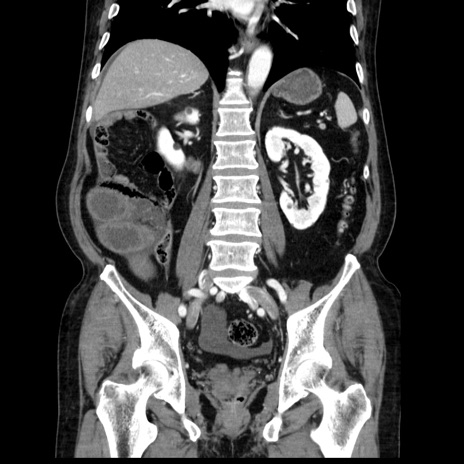

症例30(冠状断像)

【症例】80歳代男性

【主訴】臍周囲痛

【現病歴】約6時間前から臍下部痛が出現。次第に腹部膨隆・背部痛も生じてきたため来院。背部痛の場所は変化しない。

【既往歴】腎盂腎炎

【身体所見】意識清明、BT 36.3℃、BP  131/87mmHg、P 87bpm、SpO2 100%(RA)、臍周囲自発痛・圧痛あり、反跳痛なし、自発痛部位に一致して板状硬あり、腹部膨隆、腸雑音減弱、CVA tenderness両側陰性。

【データ】WBC 19600、CRP 0.33